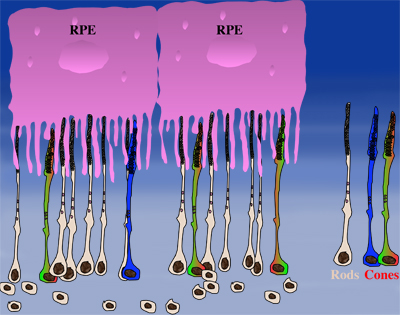

How could the observations of nutritionally deprived cones explain the dependence of cones on rods? Photoreceptor outer segments interact with the retinal-pigmented epithelium, which a single sheet of cells adjacent to the photoreceptor layer. The outer segments-retinal-pigmented epithelium interactions are vital since the retinal-pigmented epithelium provides nutrition and oxygen to PRs. Roughly 95% of all PRs in mouse and human are rods and approximately 20-30 outer segments contact one retinal-pigmented epithelium cell. Thus, only 1-2 of those retinal-pigmented epithelium-outer segment contacts are via cones. In Retinitis Pigmentosa rods die primarily due to a mutation in a rod specific gene. The loss of rods, which comprise ~95% of all photoreceptors leads to a collapse of the outer nuclear layer. During this collapse, the few remaining cone:retinal-pigmented epithelium interactions are likely perturbed (Rollover image below). If these interactions drop below a critical threshold required for the proper flow of nutrients, the loss of rods results in reduced flow of nutrients to cones. By cross-comparing 4 mouse models of Retinitis Pigmentosa we found in our studies that cone death starts always after ~90% of rods have died. This cell density thus represent the crucial threshold of remaining cells after which flow of nutrition is perturbed. This mechanism also explains why the loss of cones does not lead to rod death. Since in humans and mouse, cones are less than 5% of all PRs, the critical threshold that perturbs outer segment-retinal-pigmented epithelium interactions is not be reached. Additionally, it also explains why in cone rich species such as Zebrafish loss of cones does affect rod survival. In summary, the determining factor for the less abundant photoreceptor cell type to die when the more abundant one dies, is the local ratio between the 2 photoreceptor cell types.

| During rod cell death the cell density decreases in the outer nuclear layer (rollover first panel to see the number of rods decrease). The reduced number of rods in the outer nuclear layer results in a collapse of the ONL and put stress on the outer segment retinal-pigmented epithelium interactions (rollover second panel to detach the outer segments from the retinal-pigmented epithelium). At later stages of degeneration a retinal cross-section looks similar to what is seen in the last panel. Once this critical threshold of remaining cells is breached cones start to die due to reduced nutrient flow while the remaining rods die due to the intrinsic mutation. | ||